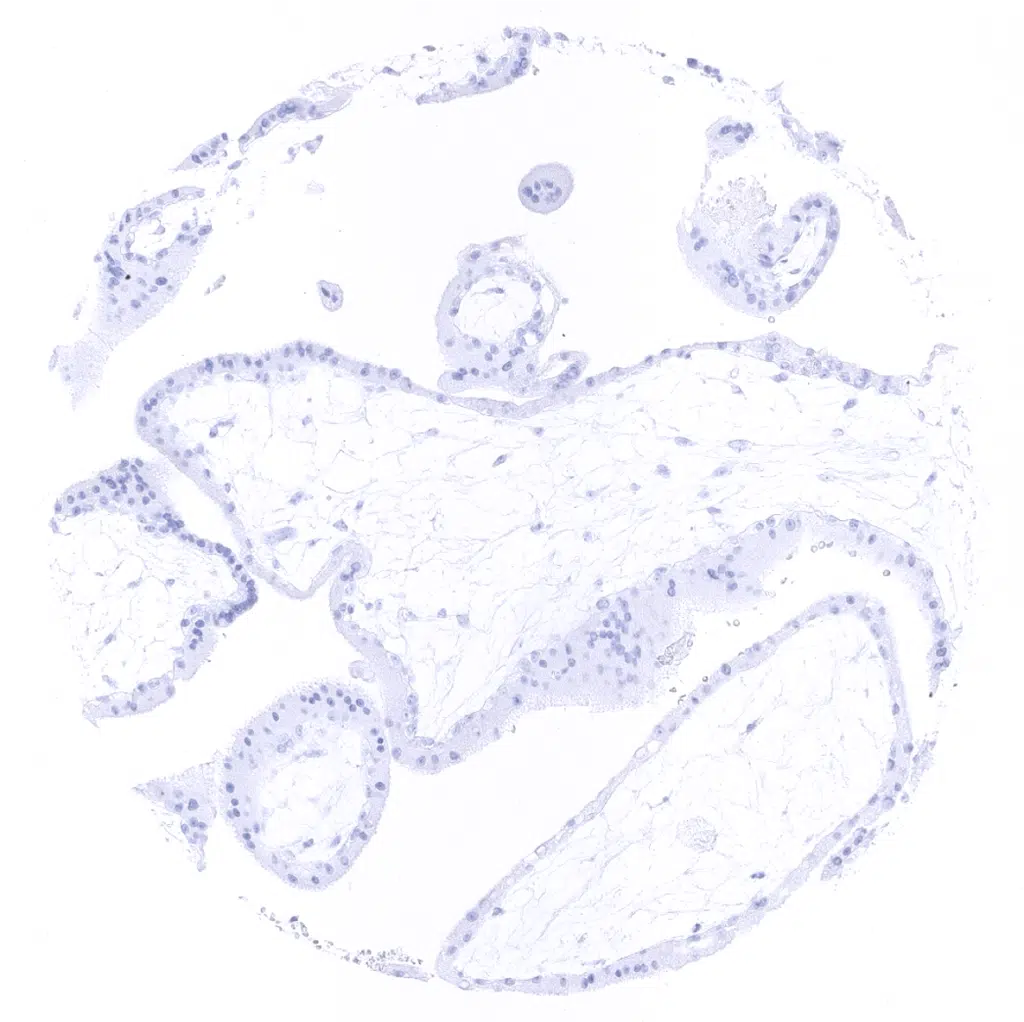

Endocervix – Strong mammaglobin positivity in endocervical glands

Endocervix – Intense mammaglobin immunostaining of endocervical glands